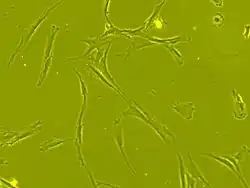

Stem cell transplantation is an important avenue for SCI research: the goal is to replace lost spinal cord cells, allow reconnection in broken neural circuits by regrowing axons, and to create an environment in the tissues that is favorable to growth.[78] A key avenue of SCI research is research on stem cells, which can differentiate into other types of cells—including those lost after SCI.[78] Types of cells being researched for use in SCI include embryonic stem cells, neural stem cells, mesenchymal stem cells, olfactory ensheathing cells, Schwann cells, activated macrophages, and induced pluripotent stem cells.[164] Hundreds of stem cell studies have been done in humans, with promising but inconclusive results.[151] An ongoing Phase 2 trial in 2016 presented data[165] showing that after 90 days, 2 out of 4 subjects had already improved two motor levels and had thus already achieved its endpoint of 2/5 patients improving two levels within 6–12 months. Six-month data was expected in January 2017.[166]

In 2014, Darek Fidyka underwent pioneering spinal surgery that used nerve grafts, from his ankle, to bridge the gap in his severed spinal cord and olfactory ensheathing cells (OECs) to stimulate the spinal cord cells. The surgery was performed in Poland in collaboration with Prof. Geoff Raisman, chair of neural regeneration at University College London's Institute of Neurology, and his research team. The OECs were taken from the patient's olfactory bulbs in his brain and then grown in the lab, these cells were then injected above and below the impaired spinal tissue.[171][38]

In March 2025, researchers reported that a paralyzed man stood for the first time after being injected of neural stem cells to treat his spinal cord injury. The first-of-its-kind study, which is not yet peer reviewed, is encouraging scientists to consider if reprogrammed stem cells can be used in the future to treat people who are fully paralyzed. Reprogrammed cells are adult cells that are reverted to an embryonic-like state, from which they can be coaxed to develop into other cell types.[173]